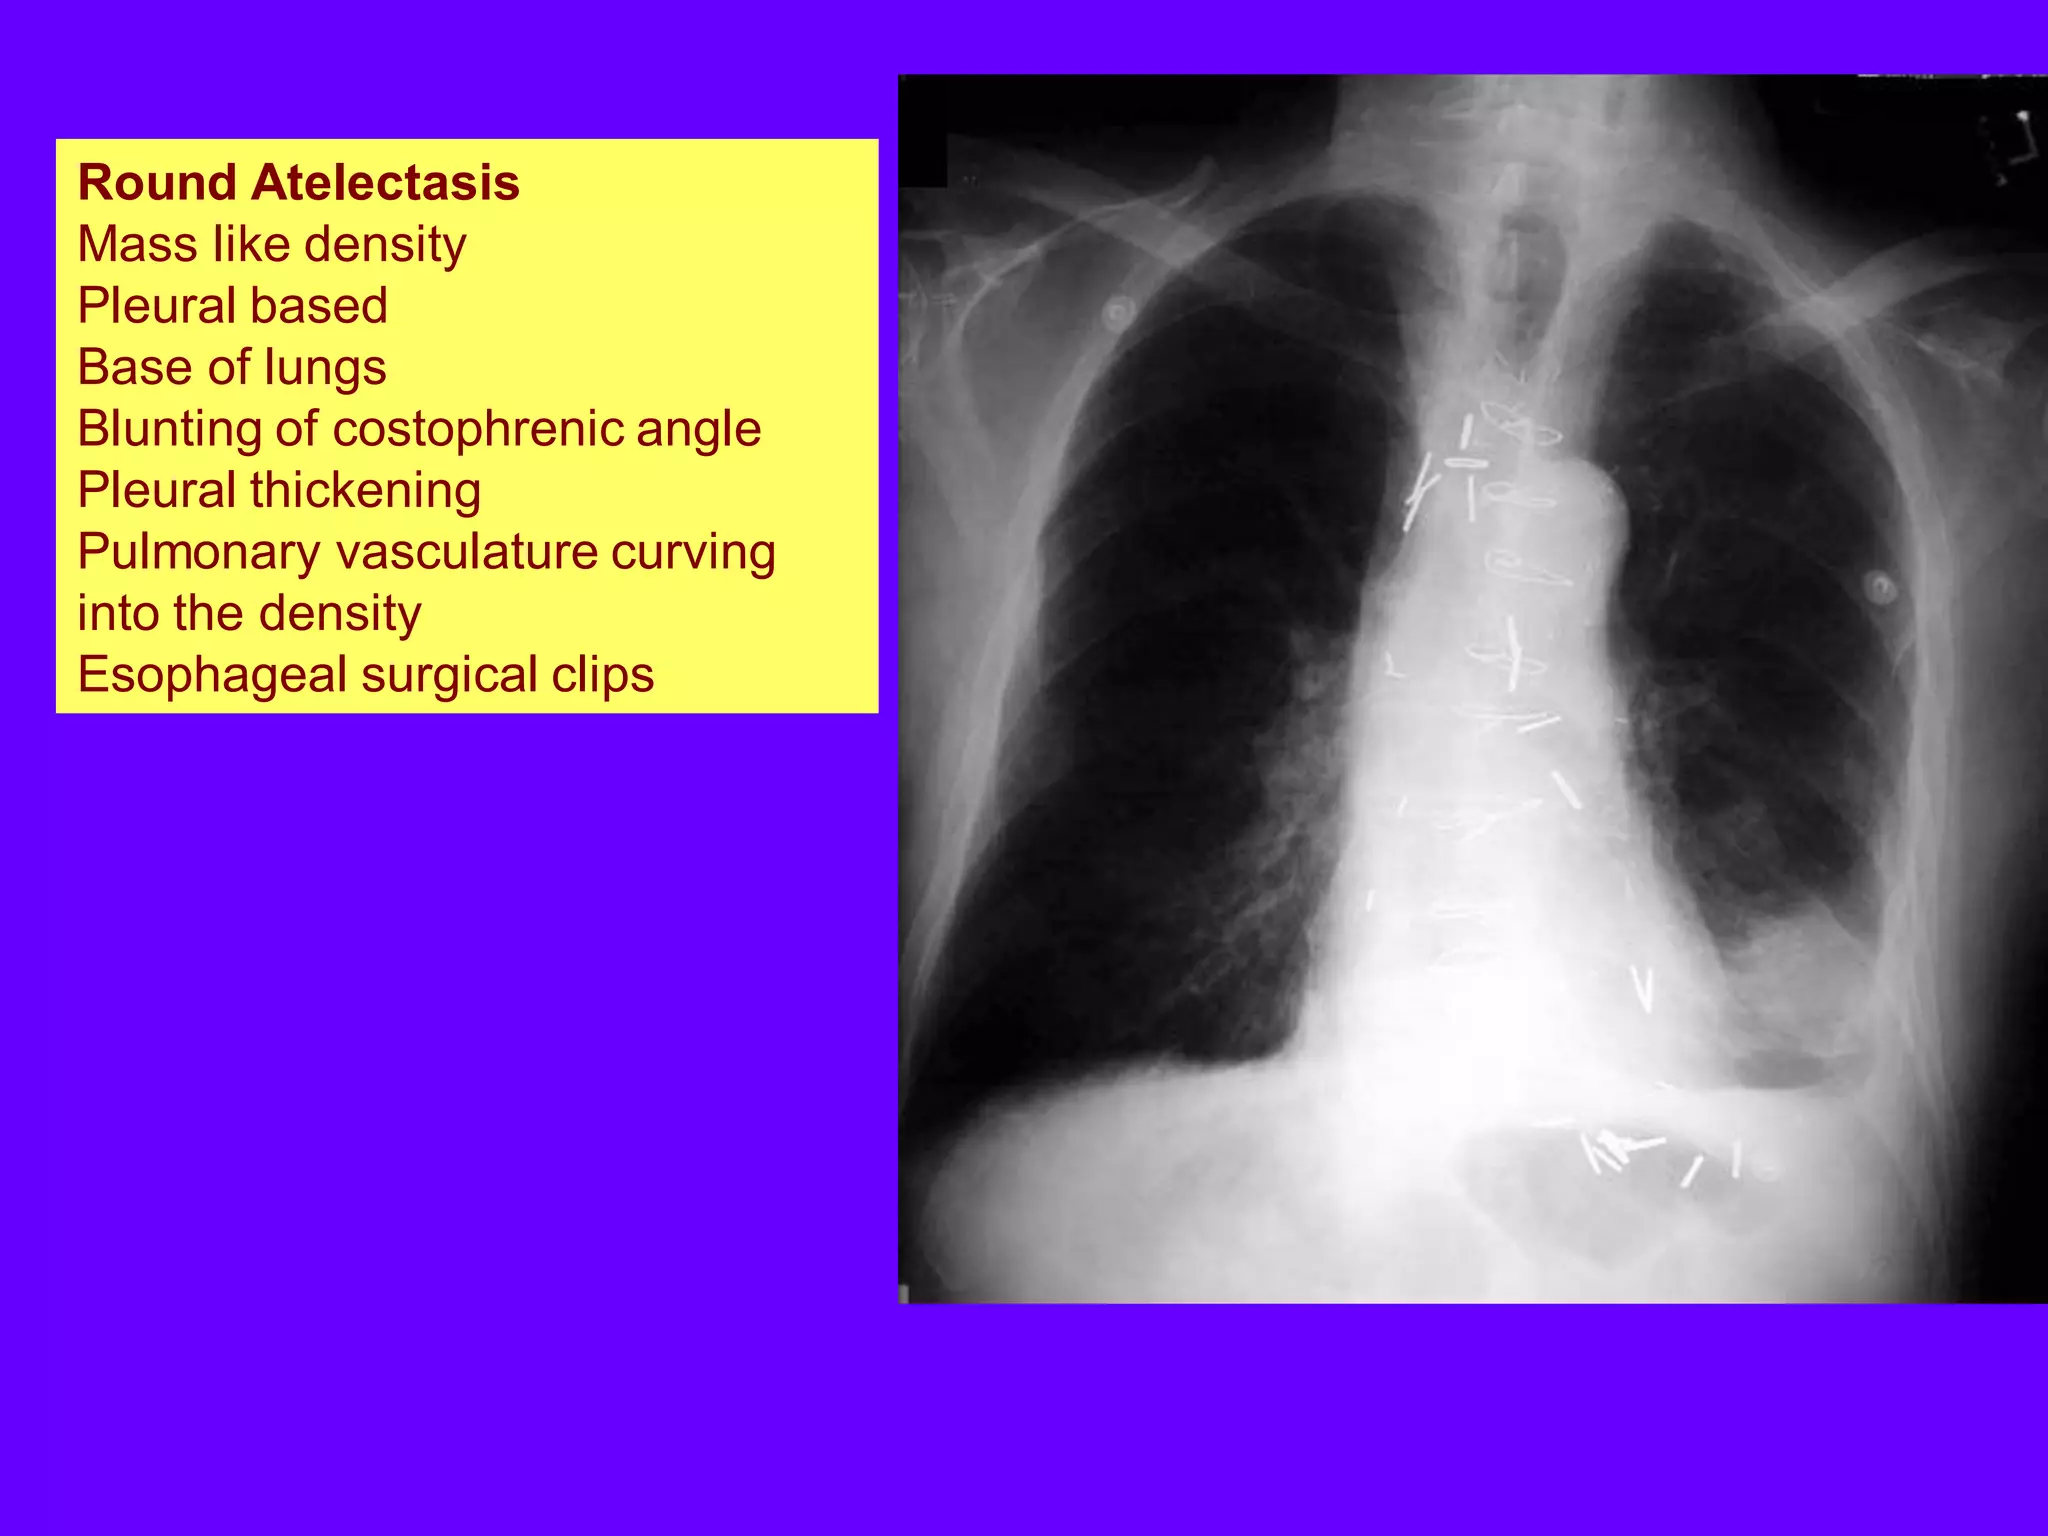

Round Atelectasis

Mass like density

Pleural based

Base of lungs

Blunting of costophrenic angle

Pleural thickening

Pulmonary vasculature curving

into the density

Esophageal surgical clips

Blunting of costophrenic angle, pleural thickening

Pulmonary vasculature curving into the density